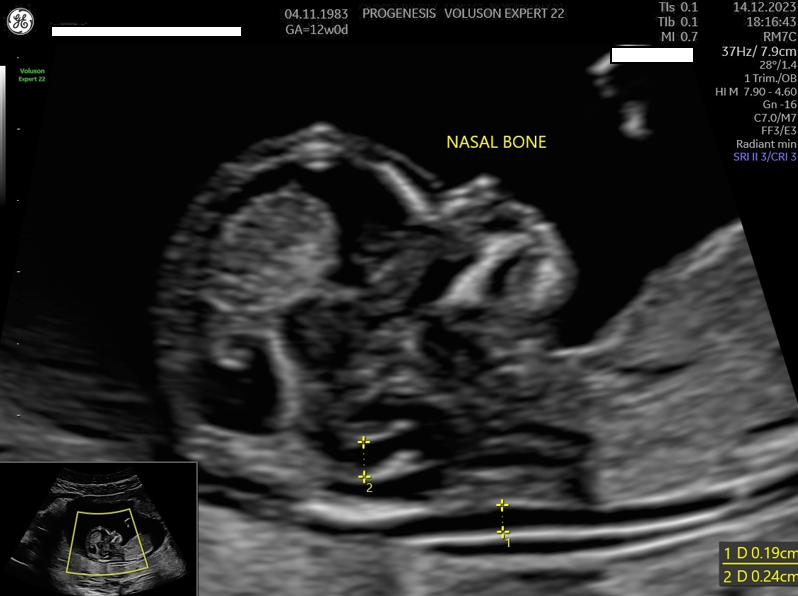

Αξιολόγηση του κινδύνου για το σύνδρομο Down και άλλων χρωμοσωμιακών ανωμαλιών.

Ο κίνδυνος μιας χρωμοσωμιακής ανωμαλίας, είναι ατομικός για κάθε γυναίκα για τη δεδομένη εγκυμοσύνη.

Εξαρτάται από την ηλικία της, το ιστορικό των προηγούμενων κυήσεων, την αξιολόγηση στο έμβρυο υπερηχογραφικών δεικτών όπως, της αυχενικής διαφάνειας, του ρινικού οστού, της ροής στην τριγλώχινα βαλβίδα και το φλεβώδη πόρο, ανατομικές ανωμαλίες που πιθανά να συνδέονται με χρωμοσωμικά/ γενετικά σύνδρομα καθώς και τη μέτρηση τριών ορμονών (PAPP-A, free βHCG και PLGF) στο αίμα της μητέρας.